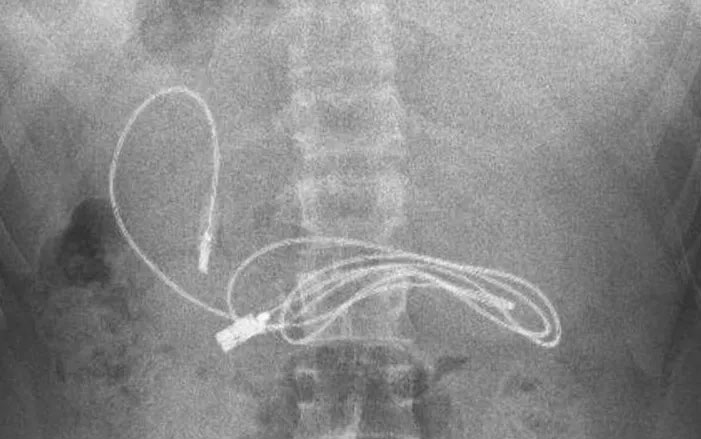

15 yaşındaki çocuğun midesinden çıkanlar şaşkına çevirdi… Akıllara durgunluk olayda kusma ve bulantı şikayetiyle ailesi tarafından hastaneye götürülen erkek çocuğunun çekilen röntgeninde, midesinde şarj kablosu ve toka olduğu tespit edildi. Bunun üzerine çocuk, ambulans ile Fırat Üniversitesi Hastanesi’ne sevk edildi.

Üniversitenin Çocuk Gastroenteroloji Hepatoloji ve Beslenme Bilim Dalı Başkanı Prof. Dr. Yaşar Doğan ve ekibi tarafından yapılan endoskopik işlemle çocuğun midesindeki kablo ve toka başarıyla çıkarıldı. Tedavisinin ardından sağlığına kavuşan çocuk taburcu edildi.

Ameliyatı gerçekleştiren Prof. Dr. Yaşar Doğan, kablonun bir ucunun ince bağırsağa geçmesi nedeniyle zorlandıklarını ifade ederek, “Hastanın kusma ve karın ağrısı şikayetleri olması üzerine sağlık kuruluşuna başvurulmuş. Orada yapılan incelemelerde hastanın midesinde kablo tespit edilmesi üzerine bize danışıldı. 112 aracılığıyla hastaya gerekli işlemi yapıp yapmayacaklarını bize sordular. Biz de hastayı bize gönderebileceklerini kendilerine ilettik.

Hasta bize geldikten sonra ön hazırlık yapıldı ve gerekli olan açlık süresinin ardından hastaya endoskopik işlem yapıldı. Endoskopik işlemle midedeki kablo çıkarıldı. Kabloyu çıkarırken açıkçası zorlandık, çünkü kablonun bir ucu ince bağırsağa geçmişti. İşlem başarılı bir şekilde sonlandırıldıktan sonra hasta sağlıklı bir şekilde evine gönderildi” dedi.